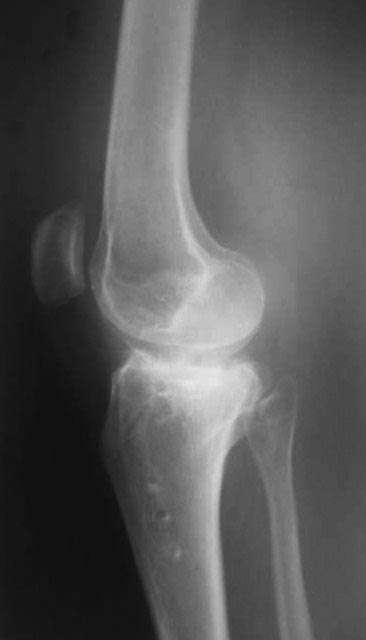

Жалобы на деформацию и нарушение функции правого коленного сустава .Внешний вид –вальгусная деформация на уровне коленного сустава .Коленный сустав стабильный, надколенник при сгибании в правильном положении.

Планируэм провести остеотомию на уровне проксимального метафиза большеберцовой кости .

При сросшемся импрессионном переломе коленный сустав в положении разгибания часто стабилен. Вальгусная нестабильность будет проявляться на дуге 30-60град. Если так, то остеотомию следует делать над уровнем прикрепления связок с ориентацией долота на межмыщелковое возвышение. Костная пластика обязательна. Пластина отмоделированая под наружный мыщелок (блокирование не принципиально). Томофикс для этой поверхности не подойдет. Гиперкоррекция около 5 град.